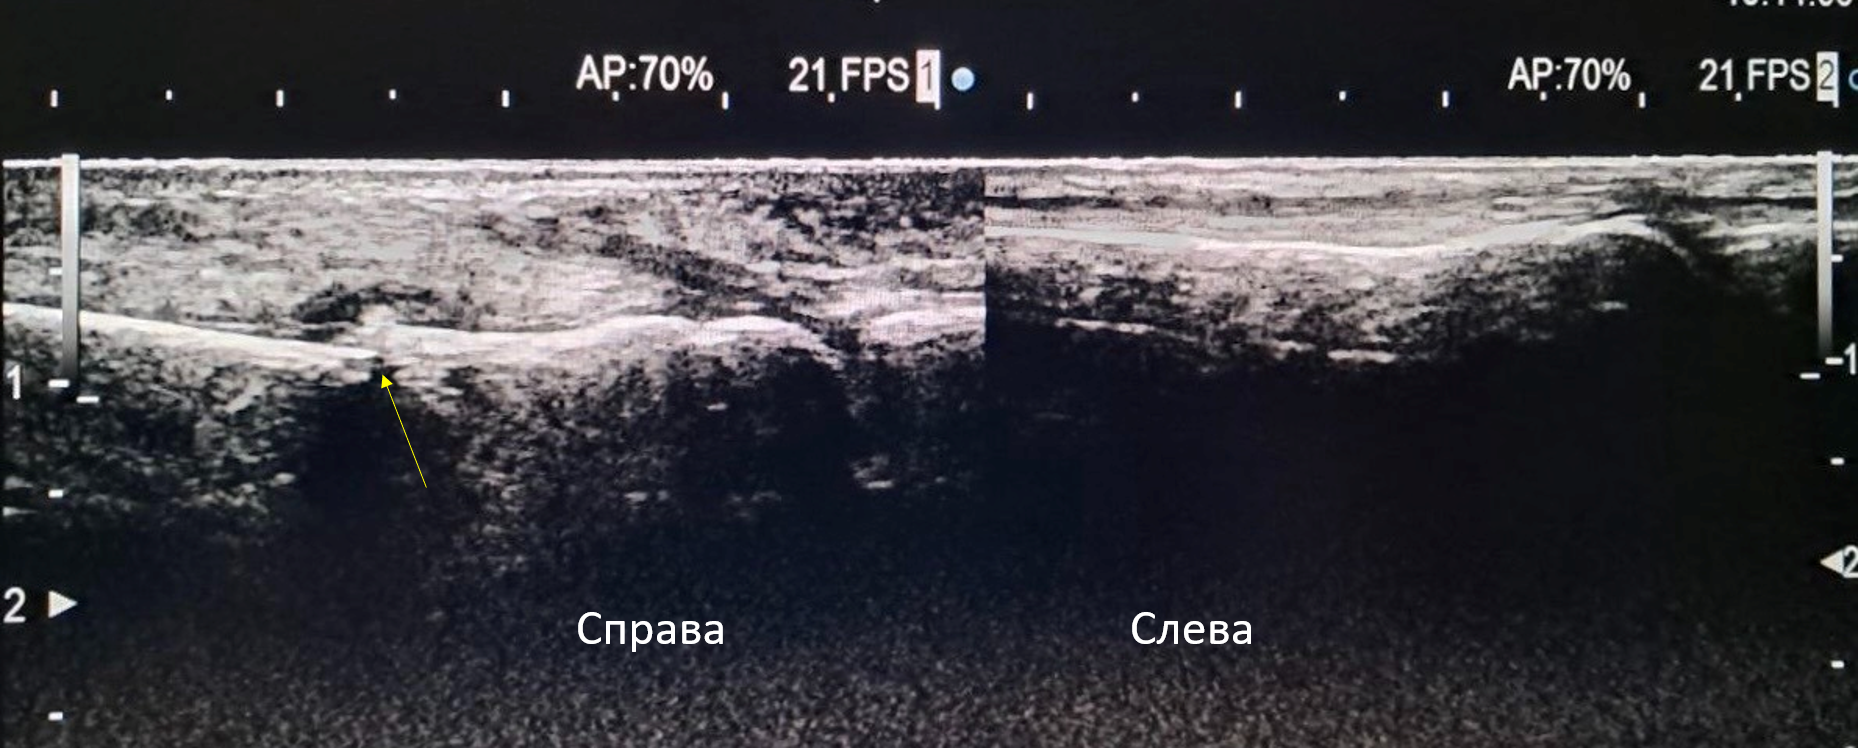

В зоне интереса (область локальной болезненности на стопе справа по тыльной поверхности) лоцируется прерывистость контура третьей плюсневой кости ближе к плюсне-фаланговому суставу со смещением костных фрагментов.

Над областью перелома имеется небольшая надкостная гематома размером 7,5 х 0,6 мм.

Отмечается утолщение мягких тканей на данном участке (толщина справа 7,5 мм, слева 4 мм). При ЦДК в области перелома — умеренное усиление кровотока.

1) ультразвуковое изображение в В-режиме: сравнение правой (область перелома) и левой (норма) сторон на уровне 3 плюсневой кости,